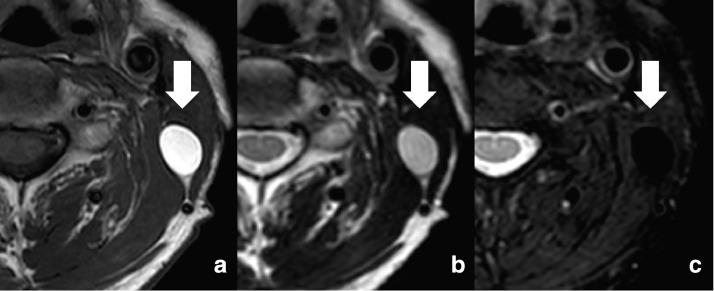

Antibiotic ointments are often used to treat or prevent infections in surgical wounds. However, due to a dearth of reports on adverse effects, the complications of the use of such ointments, especially possible long-term effects, are largely unknown. We experienced a unique case of a cystic lesion that developed after surgical site infection treated with gentamicin ointment in a 62-year-old man who underwent subtotal glossectomy for tongue cancer. The antibiotic ointment that was applied following abscess drainage remained there, replacing the abscess cavity and forming an oval mass. The lesion was found incidentally on follow-up MR examination to monitor cancer recurrence. On both T1- and T2-weighted images, it showed high-intensity reflecting oily base material, constituting the ointment, which appeared to be a fat-containing tumor such as a lipoma that had arisen at the surgical site. Echo-guided drainage extracted the ointment, which was seemingly unaltered from the time it was applied 11 months before. We describe the clinical course and imaging findings to acknowledge this potential adverse effect associated with topical antibiotic treatment for surgical site infection.

抗生素软膏常用于治疗或预防手术伤口感染。然而,由于关于不良反应的报道较少,此类软膏使用的并发症,尤其是可能的长期影响,在很大程度上尚不明确。我们遇到了一例独特的囊性病变病例,该病例发生在一名62岁因舌癌接受舌次全切除术的男性患者身上,其手术部位感染后用庆大霉素软膏治疗。脓肿引流后涂抹的抗生素软膏留在了原处,取代了脓肿腔并形成了一个椭圆形肿块。该病变是在随访磁共振检查以监测癌症复发时偶然发现的。在T1加权和T2加权图像上,它均显示出高强度信号,反映了构成软膏的油性基质,看起来像是手术部位出现的含脂肪肿瘤,如脂肪瘤。超声引导下引流抽出了软膏,其外观与11个月前涂抹时似乎没有变化。我们描述了该临床过程和影像学表现,以认识到这种与手术部位感染局部抗生素治疗相关的潜在不良反应。